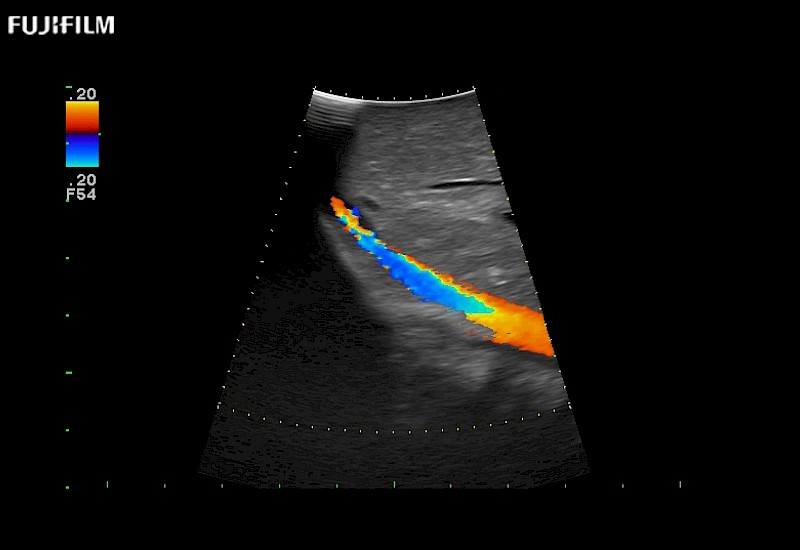

Multi-Parametric imaging modalities

Extraordinary high-resolution digital imaging

- Instant feedback on tumor margin delineation

- Instant feedback on tumor margin delineation

- Exceptional near and far-field resolution

- Instant feedback on tumor margin delineation

- Instant feedback on tumor margin delineation

- Instant feedback on tumor margin delineation

- Instant feedback on tumor margin delineation

- Instant feedback on tumor margin delineation

- Instant feedback on tumor margin delineation

- Instant feedback on tumor margin delineation

- Instant feedback on tumor margin delineation